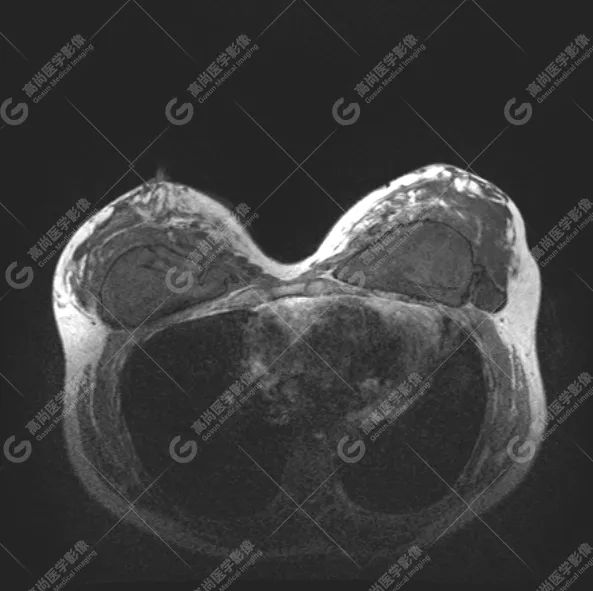

病例 6:乳腺假体植入术后 10 余年,左侧乳腺触及硬结伴疼痛

1、双乳假体包膜完全破裂;左侧腋窝区、胸大肌内、胸大肌与胸小肌间隙、腺体内及双侧假体周围多发注射物渗漏并液化坏死;

2、左侧假体破裂导致的左腋部硅胶相关性淋巴结病,信号复杂。